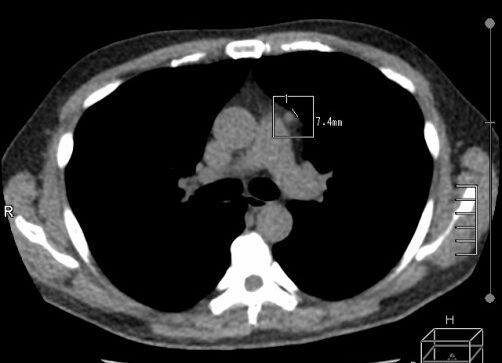

胸部X光在檢測縱膈腔方面有其限制,但CT能更精確發現異常。這篇研究顯示,縱膈腔病變在第3類中並不多,但比例相對較高(5例/9例占56%)。至於小於1公分的胸腺腫塊則被歸為第2類,但仍須密切追蹤與評估。一名49歲醫療儀器公司高階主管來本院健檢,於2015及2016年時的LDCT發現前縱膈腔有一個穩定小結節(7.4 mm) (圖3),分類為第2類,後來年度健檢他選擇一般胸部X光為主的方案。直到2023年再次LDCT檢測結果發現原本前縱膈腔小結節長大成約6公分的腫塊,此時可歸屬到第3類,經轉診手術證實為胸腺瘤WHO分類AB型,幸好只有顯微下腫瘤包囊受侵犯。

圖3:2015年前縱膈腔小結節 (7.4mm),2023年12月顯示前縱膈腔腫塊(58.5 mm x 35.2 mm)